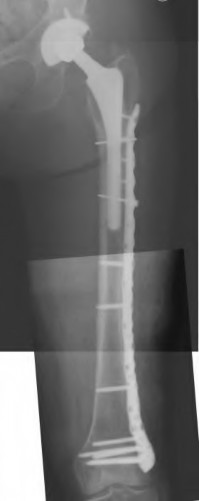

A 72-year-old male presents 2 years status post fixation of an impending pathologic right femur fracture due to metastatic renal cell carcinoma. He is minimally ambulatory due to pain. Despite radiation therapy, there has been progression of the lesion with extensive cortical bone loss, which is shown in Figure A. A proximal femoral replacement arthroplasty is performed without complications, and is demonstrated in Figure B. Which of the following is true regarding this patients post-operative course?

Figure A shows a lytic lesion of the proximal femur with an intramedullary implant. Figure B shows a proximal femoral replacement.